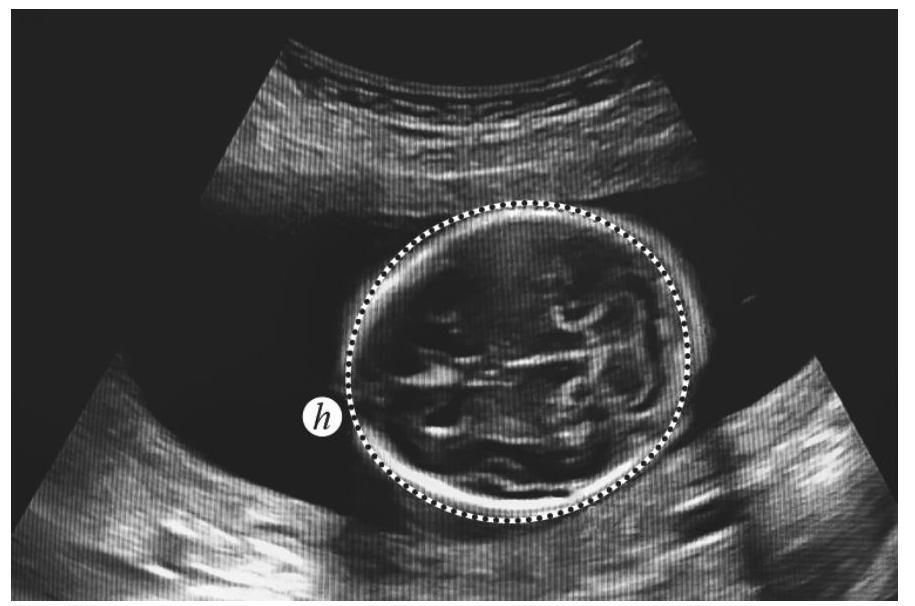

Een zwangerschapsecho is een afbeelding van een ongeboren baby. Zie foto 1. Een echo wordt onder andere gebruikt om vast te stellen hoe lang een vrouw al zwanger is.

Op de echo kan de afstand$avan de bovenkant van het hoofdje tot de onderkant van de billen worden gemeten.

foto 1